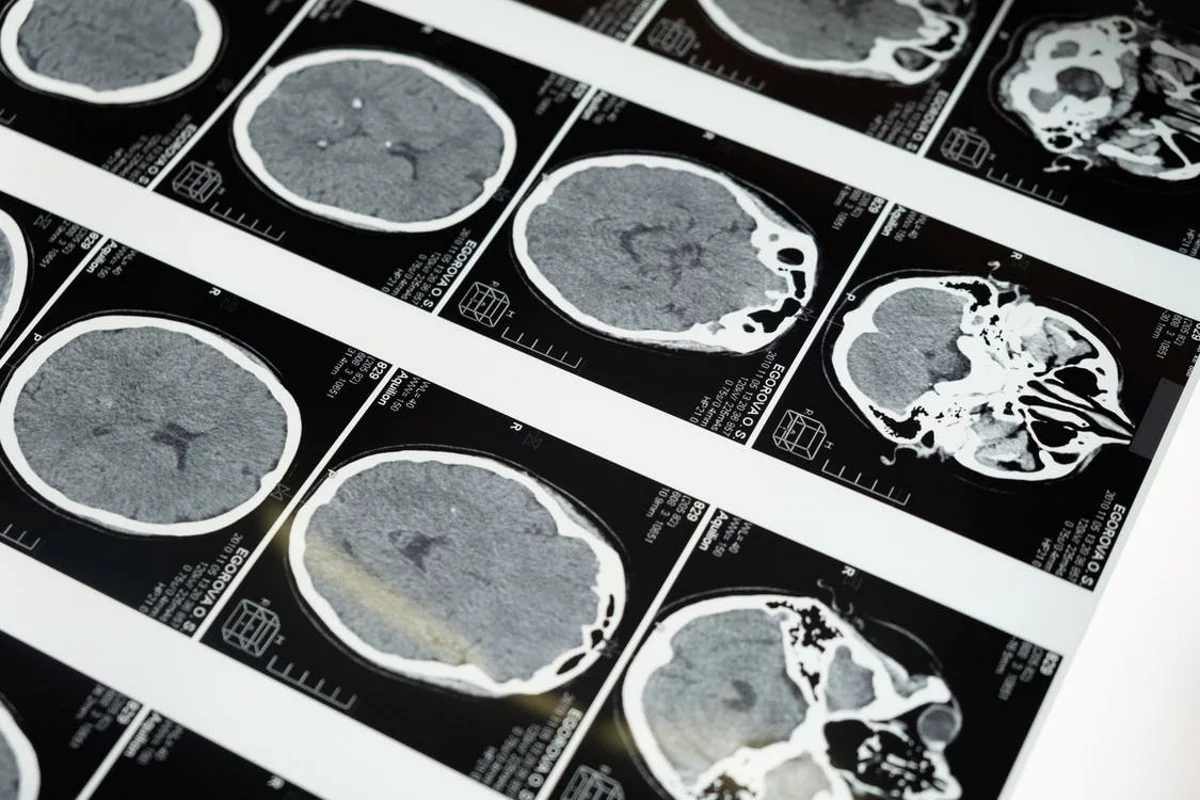

Además, los pacientes podrán someterse a más pruebas resultado de los avances científicos en neurología, tales como una tomografía computarizada (TC) o una resonancia magnética. Asimismo, se pueden hacer tomografías por emisión de positrones (PET) u otros escáneres cerebrales. Sin embargo, solamente se podrá confirmar el diagnóstico con una biopsia.